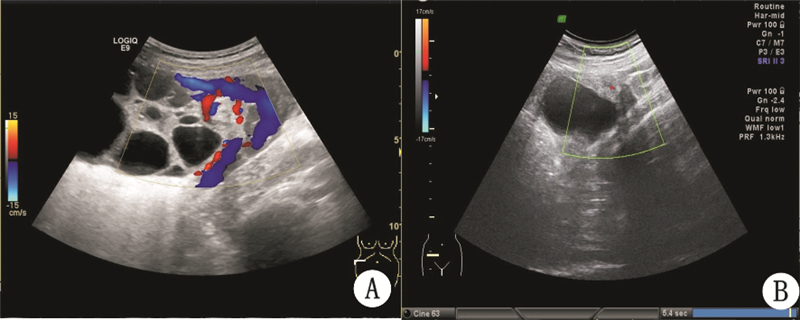

40例中不全扭转(即扭转小于360°)13例;完全扭转不伴坏死18例(扭转一圈以上);完全扭转伴卵巢坏死(扭转一圈以上,伴卵巢或输卵管坏死)9例。不同程度卵巢囊肿蒂扭转超声表现及患者情况见表 1。典型图例见图 1和图 2。

| A:不全扭转的蒂部“麻花样”血流;B:完全扭转伴坏死点状血流 图 1 卵巢扭转血流图 |

妊娠时附件上升进入腹腔,宫底推开附件周围肠管,卵巢蒂部以其长轴为中心发生不同程度的扭转,较长的蒂部形成实性团块状组织,蒂部与卵巢一起形成大小不等的囊、实双块征。附件扭转时,蒂部血管受压,不全扭转或扭转程度较轻时,血流丰富,呈“麻花样”(图 1A),动、静脉频谱均可探及。完全扭转时因静脉回流完全被阻断,PW仅见高阻动脉频谱或舒张期血流消失(图 2A),静脉淤血,瘤体内高度充血,增大的瘤体刺激腹膜,引起急性下腹剧痛,探头触痛实验阳性;扭转程度重时间长时,仅见星点状血流(图 1B),PW为舒张期血流消失的动脉频谱(图 2B),或动静脉血流均消失,组织坏死,部分伴渗出液形成,与周围组织黏连,超声检查时发现瘤体边界不清,内部结构混乱,囊肿周围可见少量游离液体。因此二维超声可仔细寻找囊肿的蒂部和囊、实双块征及蒂部的探头触痛实验来诊断附件扭转的有无;彩色多普勒超声可以根据蒂部血流信号的有无及频谱的动静脉类型来判断扭转的程度[10]。